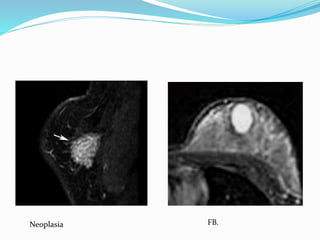

Neoplasia FB.

Neoplasia

FB

2) Masas: lesiónque ocupa un espacio dentro de la mama. Se describe: • Forma:  Redonda  Oval  Lobulada  Irregular quiste Malignidad